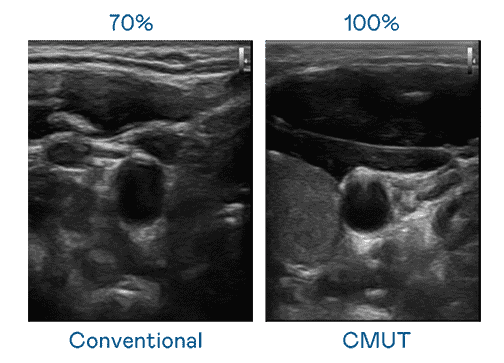

CMUT 技术是一种用电容式微机电元件来产生超音波讯号的技术。。。。与传统 PZT 压电式技术相比,,,CMUT 频宽增加 30%,,,,更宽频的超音波讯号让影像解析度大幅提升,,,,是实现高影像品质医疗超音波扫描、、、促进精准医疗发展的关键技术。。

大频宽带来超清晰影像

超音波影像的解析度高低,,,首先取决于探头能发出的讯号频宽。。。壹号平台 CMUT 可提供高清晰的超音波讯号,,,提供高频宽、、、、高灵敏度、、影像纹理细节更高的超音波影像,,协助医护人员缩短影像判读时间及利用精准的医疗影像进行诊断。。。